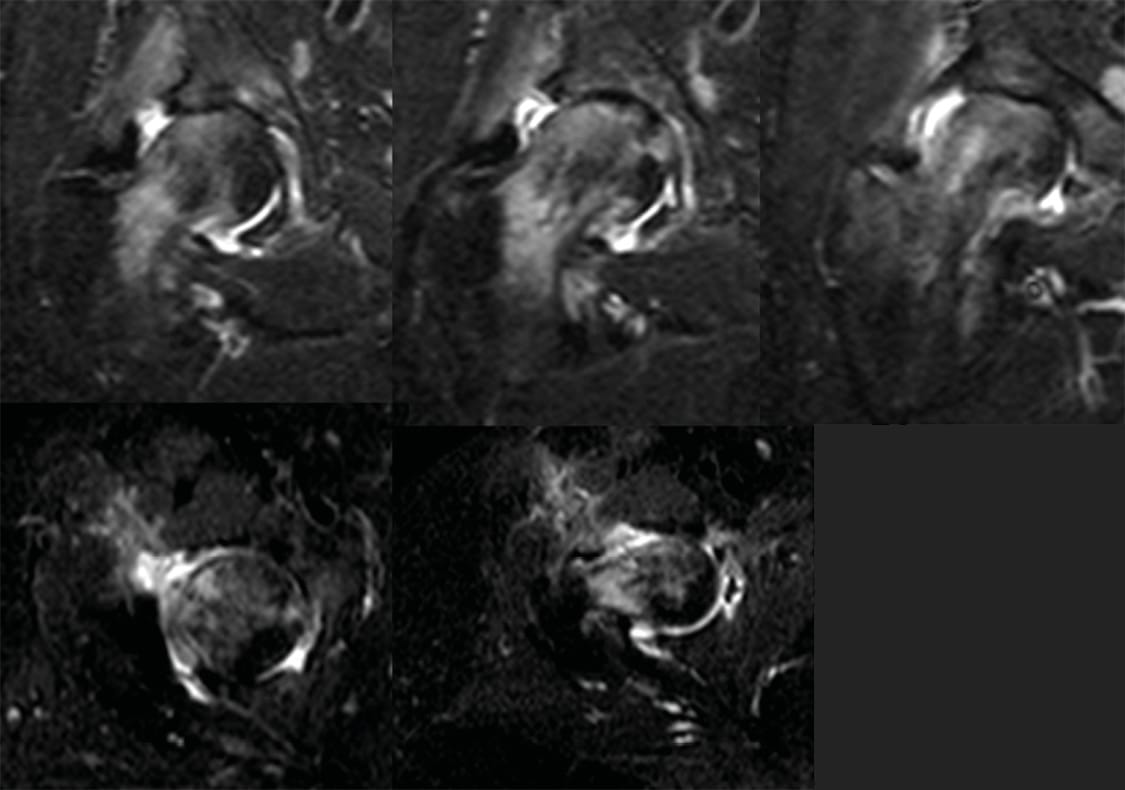

An empirical antibiotic therapy with Vancomycin and Ceftazidime was started. After one week (day 8) of culture in enriched media, Granulicatella adiacens was recovered and, according to the antibiogram, ATB was adapted to Ceftriaxone 1g/12 hours + Gentamicin 80 mg/ 8 hours for four weeks following by 8 weeks of minocycline orally. Sensitivity to Vancomycin was also reported. As additional data, the samples from the arthroscopy were negative. In addition, given the association of this germ with bacterial endocarditis, although she was asymptomatic, an echocardiogram was performed, and endocarditis was concomitantly diagnosed. Two weeks after treatment, she started again with pain in the right hip, so xray, laboratory and hip MRI were repeated. Xray showed chondrolysis with loss of the joint space. The laboratory values were similar to those of the initial diagnosis, while MRI showed hyperintensity in the femoral head in the STIR sequence, interpreted as subchondral necrosis secondary to septic arthritis. (Figures 3-4).

We therefore decided to perform open debridement, reaming the acetabular cavity and placing an articulated custom-made spacer coated with Vancomicyn loaded cement. Two grams of Vancomycin were added to each dose of 40 grams of cement. (Figure 5).